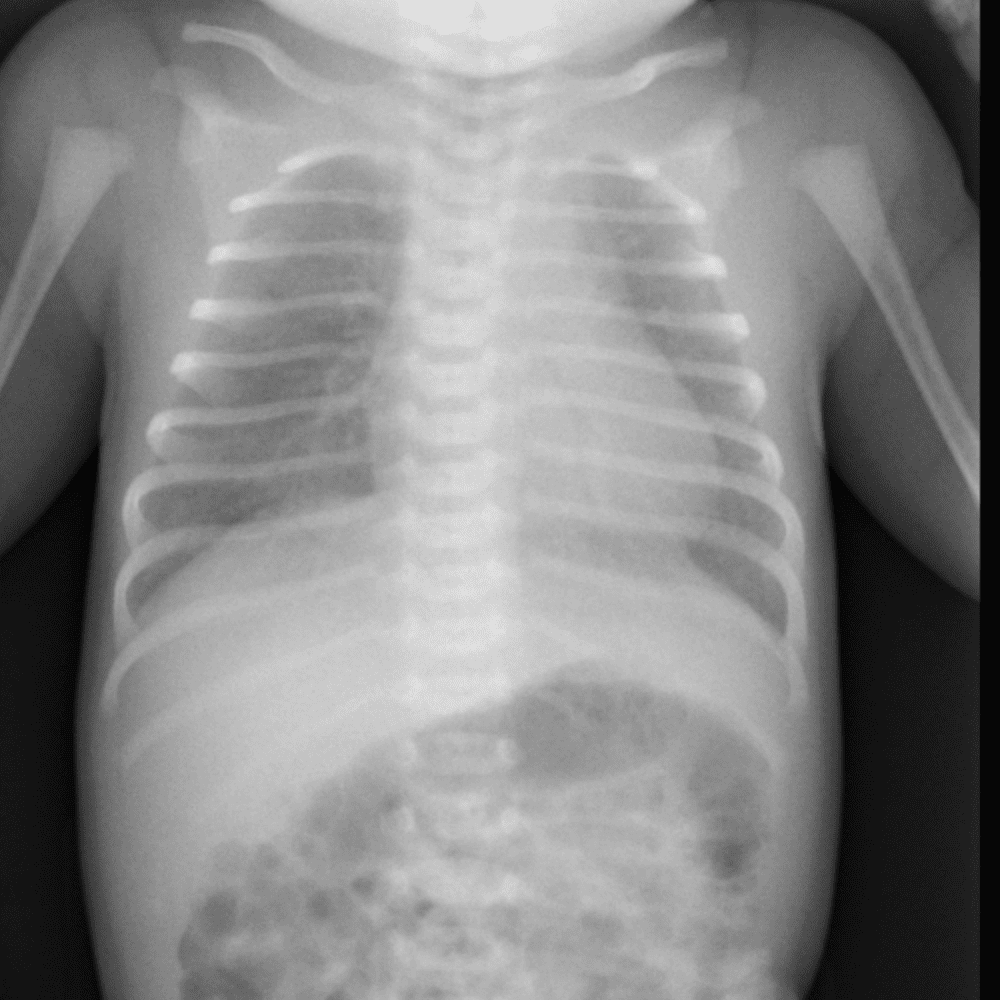

Peds Chest

Practice

Simulates call by including subtle or difficult cases and some normals.

50 cases